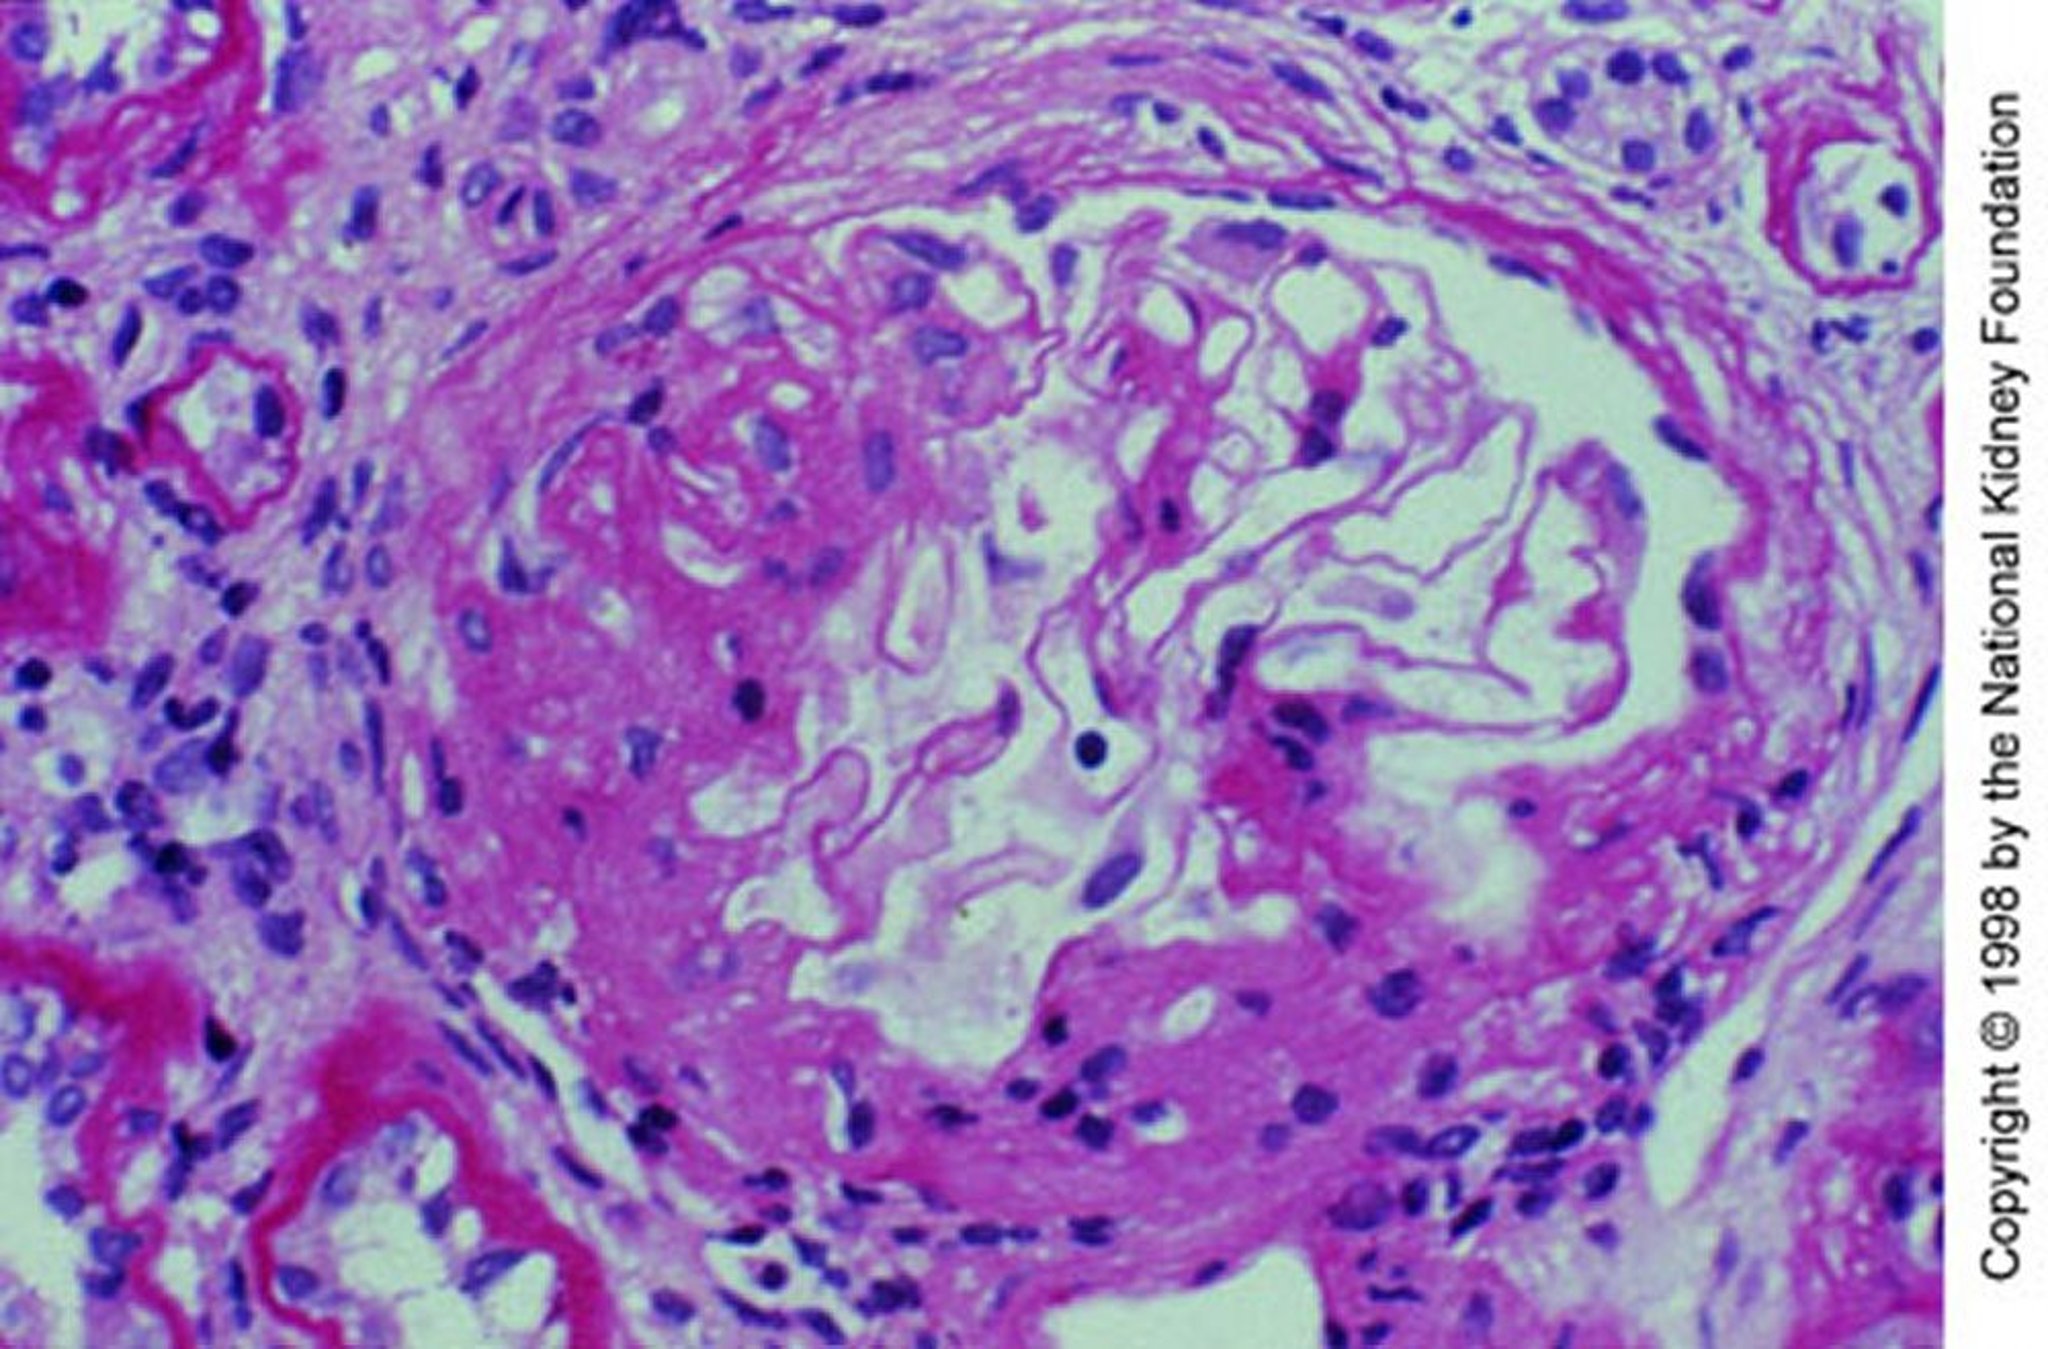

IgA-Nephropathie (mesangiale Expansion)

Mesangiale Expansion mit segmentaler Sklerose (periodische Säure-Schiff-Färbung, ×200).

Image provided by Agnes Fogo, MD, and the American Journal of Kidney Diseases' Atlas of Renal Pathology (see www.ajkd.org).